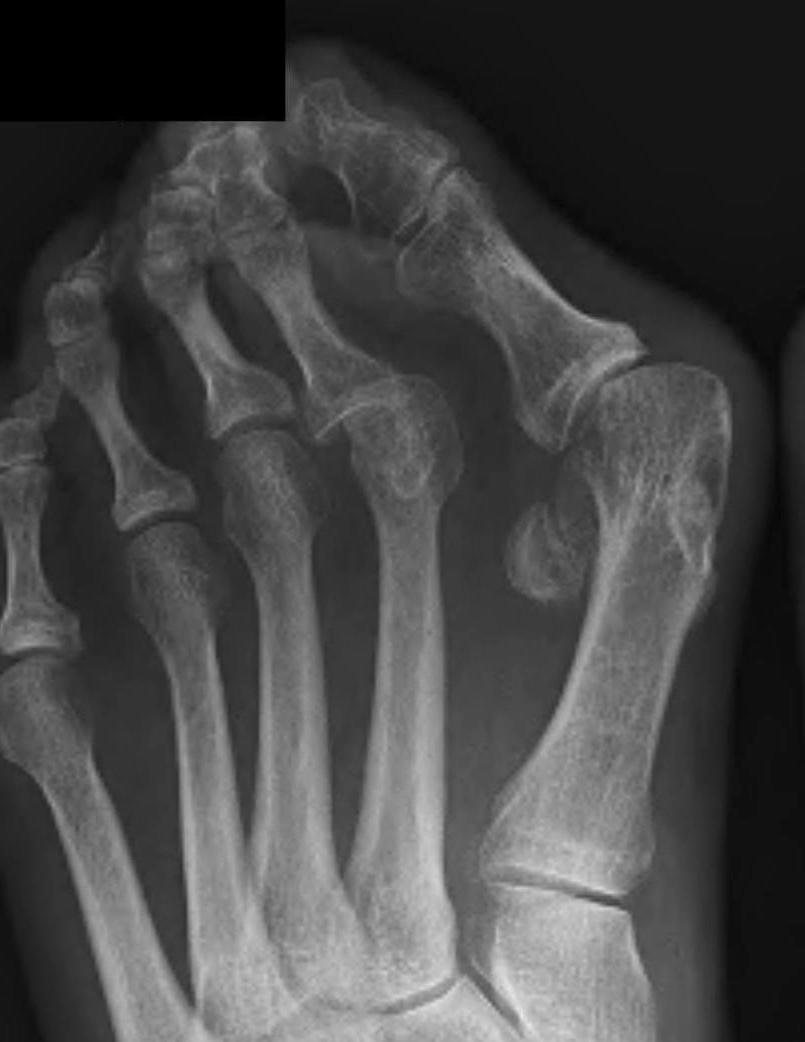

Mann Classification

1. Congruent

2. Incongruent - mild / moderate / severe

3. Degenerative

Incongruent

| Mild | Moderate | Severe |

|---|---|---|

|

HVA < 30° IMA < 15° Lateral sesamoid < 50% uncovered |

HVA 30 - 40° IMA 15 - 20o Lateral sesamoid 50 - 75% uncovered |

HVA > 40° IMA > 20° Lateral sesamoid > 75% uncovered |

Hallux valgus with early degeneration